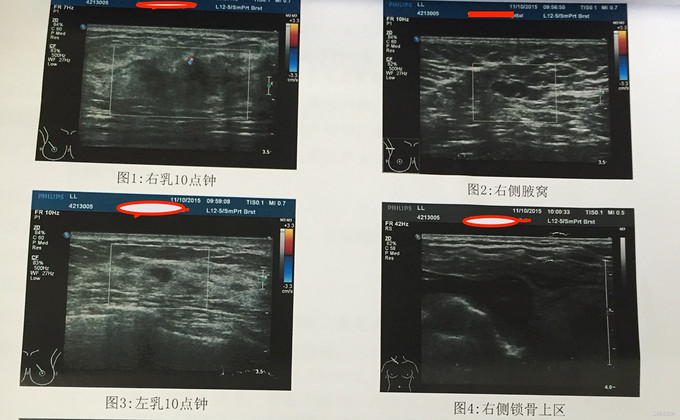

患者因“发现右乳包块3+年”入院。3+年前患者体检发现右乳包块,不伴其他直觉症状,未予重视。5+天前患者感包块较增大,就诊于当地医院。右乳包块,穿刺活检示:浸润性癌(WHO 2级),求进一步治疗,就诊于我院。

查体:双乳对称,双乳头多孔无色透明液体,量多,右乳11-12点方向可扪及一质硬包块,大小约3*3*3cm,形态不规则,边界不清,活动度差,无压痛,余(-)。 穿刺同前

入院诊断:1、右乳包块:癌?2、双乳多孔溢液:导管扩张 治疗:已行右乳单纯切除+右腋窝1-3水平淋巴结清扫。 术后病检示:右乳浸润性导管癌(中分化/2级)伴导管内癌(高核级伴粉刺样坏死)。见脉管内癌栓。 IHC:ER(+,90%),PR(+,80%),Her2(1+),ki-67(15%)。 送检淋巴结:右腋1-2水平(1/23)枚,查见癌转移,余(-) 术后诊断:1、右乳浸润性导管癌(T2N1M0)2、双乳多孔溢液:导管扩张